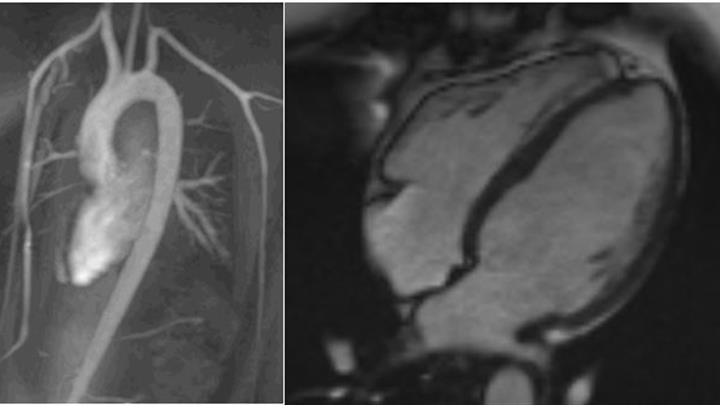

Sydämen magneettitutkimusta käytetään yhä useammin sydänsairauden syyn selvittelyssä, mikäli se ei ole selvinnyt ultraäänitutkimuksen ja muiden perusselvittelyiden jälkeen. Magneettitutkimus perustuu voimakkaan magneettikentän aiheuttamiin signaaleihin kudoksesta ja sillä on hyvä erotuskyky muun muassa sydämen rakenteisiin.

Sydämen magneettitutkimus antaa tarkkaa tietoa sydämen rakenteista ja toiminnasta.